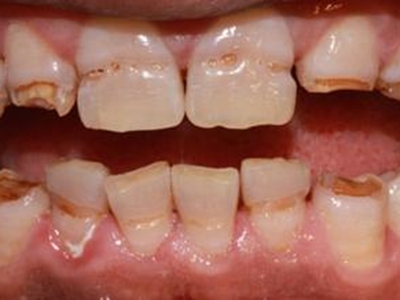

牙齿

条纹

牙釉质发育不全牙齿中间有棕色条纹图

重度牙釉质发育不全患者牙齿表面呈棕褐色,牙釉质大面积缺损,其上有并列的条状凹陷,部分牙尖缺损,导致咬合关系被破坏,并出现疼痛等自觉症状。

白斑

牙釉质发育不全牙齿有白斑图

牙釉质发育不全程度较轻时,导致牙齿表面发白,出现白斑样釉质,导致牙齿透明度下降,同时牙根部位出现棕褐色的带状凹陷,像是没刷牙一样。